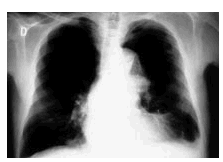

Un paciente de 79 años de edad con el antecedente de enfisema pulmonar severo fue diagnosticado de una rotura de la porción más distal de un aneurisma de la aorta torácica descendente. Se consideró candidato a tratamiento endovascular. Mediante una arteriotomía ilíaca común derecha se introdujeron 3 endoprótesis tipo stent que recubrieron 23 cm de la aorta torácica (figs. 1 A y B). En el seguimiento a 3 meses, el paciente permanece asintomático y con buena calidad de vida.

Fig. 1 B.